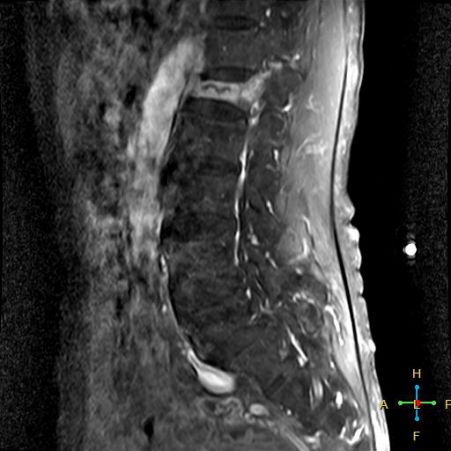

3 恶性压缩性骨折 椎体上下径变窄而前后径增大,椎体后部皮质后突,后角一般表现圆钝,无上翘,常呈球形突出,致椎管狭窄,即膨胀性盘状破坏,硬膜囊和脊髓受压。

——恶性压缩性骨折MR信号特点—— 由于肿瘤组织的侵犯,T1WI上椎体呈弥漫性低信号,T2WI呈高信号,增强扫描呈明显不均匀强化。

转移瘤 椎弓根改变:椎弓根膨大仅见于恶性压缩性骨折,故为其特异性,可作为鉴别诊断的依据。

椎旁软组织肿块:在转移瘤中,受累椎体周围多出现分叶状或肿瘤样软组织肿块,此征象仅见于恶性压缩性骨折。故,椎旁薄环状软组织与瘤样软组织肿块是鉴别骨折性质较有特征性的征象。

——恶性压缩性骨折—— 扁平形或倒楔形 跳跃性分布(转移瘤) 椎间盘不受累 T1WI均匀低信号 后角圆钝,膨胀性盘状破坏 椎弓根受累、膨大 椎旁分叶状及肿瘤样软组织肿块